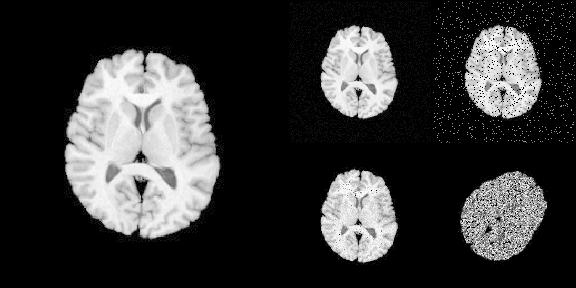

#> signature: (image, noise_model, noise_parameters)The following R code translates Python code into R:

# >>> img = ants.image_read(ants.get_ants_data('r16'))

img <- ants$image_read(ants$get_ants_data('r16'))

# >>> noise_image1 = ants.add_noise_to_image(img, 'additivegaussian', (0.0, 1.0))

noise_image1 <- ants$add_noise_to_image(

img, 'additivegaussian',

noise_parameters = tuple(0.0, 1.0)

)

# >>> noise_image2 = ants.add_noise_to_image(img, 'saltandpepper', (0.1, 0.0, 100.0))

noise_image2 <- ants$add_noise_to_image(

img, 'saltandpepper',

noise_parameters = tuple(0.1, 0.0, 100.0)

)

# >>> noise_image3 = ants.add_noise_to_image(img, 'shot', 1.0)

noise_image3 <- ants$add_noise_to_image(

img, 'shot',

noise_parameters = 1.0

)

# >>> noise_image4 = ants.add_noise_to_image(img, 'speckle', 1.0)

noise_image4 <- ants$add_noise_to_image(

img, 'speckle',

noise_parameters = 1.0

)

noise_image4 <- trans$apply_to_image(noise_image4)To load imaging data into R

# Use [] to convert ANTsImage into R array

is.array(img[])

#> [1] TRUE

# plot via R

layout(matrix(c(1,1,2,3,1,1,4,5), nrow = 2, byrow = TRUE))

par(mar = c(0.1, 0.1, 0.1, 0.1), bg = "black", fg = "white")

pal <- grDevices::gray.colors(256, start = 0, end = 1)

image(img[], asp = 1, axes = FALSE,

col = pal, zlim = c(0, 255), ylim = c(1, 0))

image(noise_image1[], asp = 1, axes = FALSE,

col = pal, zlim = c(0, 255), ylim = c(1, 0))

image(noise_image2[], asp = 1, axes = FALSE,

col = pal, zlim = c(0, 255), ylim = c(1, 0))

image(noise_image3[], asp = 1, axes = FALSE,

col = pal, zlim = c(0, 255), ylim = c(1, 0))

image(noise_image4[], asp = 1, axes = FALSE,

col = pal, zlim = c(0, 255), ylim = c(1, 0))